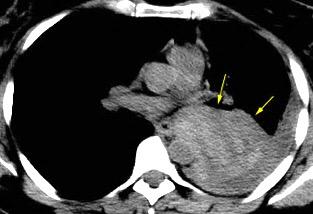

40. EMPIEMA PLEURAL. ORIGEN HEPÁTICO

Colecciones “inflamatorias” abdominales llegan al tórax vía el hiato esofágico o por vía transdiafragmática

Afectación transdiafragmática: 5,6-43,7% de quistes hepáticos. “Área desnuda” del hígado.

Panda A et al. “Straddling Across Boundaries”. Thoracoabdominal Lesions: Spectrum and Pattern Approach. Curr Probl Diagn Radiol. 2015 Área desnuda. El hígado en contacto directo con el tendón central del diafragma. Contiene el hiato de VCI.